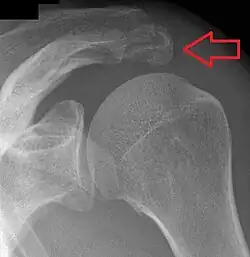

Shoulder

Os acromiale.

• An os acromiale forms when any of its four ossification centers fail to fuse. These four ossification centers are called (from tip to base) pre-acromion, meso-acromion, meta-acromion, and basi-acromion. In most cases, the first three fuse at 15–18 years, whereas the base part fuses to the scapular spine at 12 years. Such failure to fuse occurs in between 1% and 15% of cases.[23][24] It rarely causes pain.